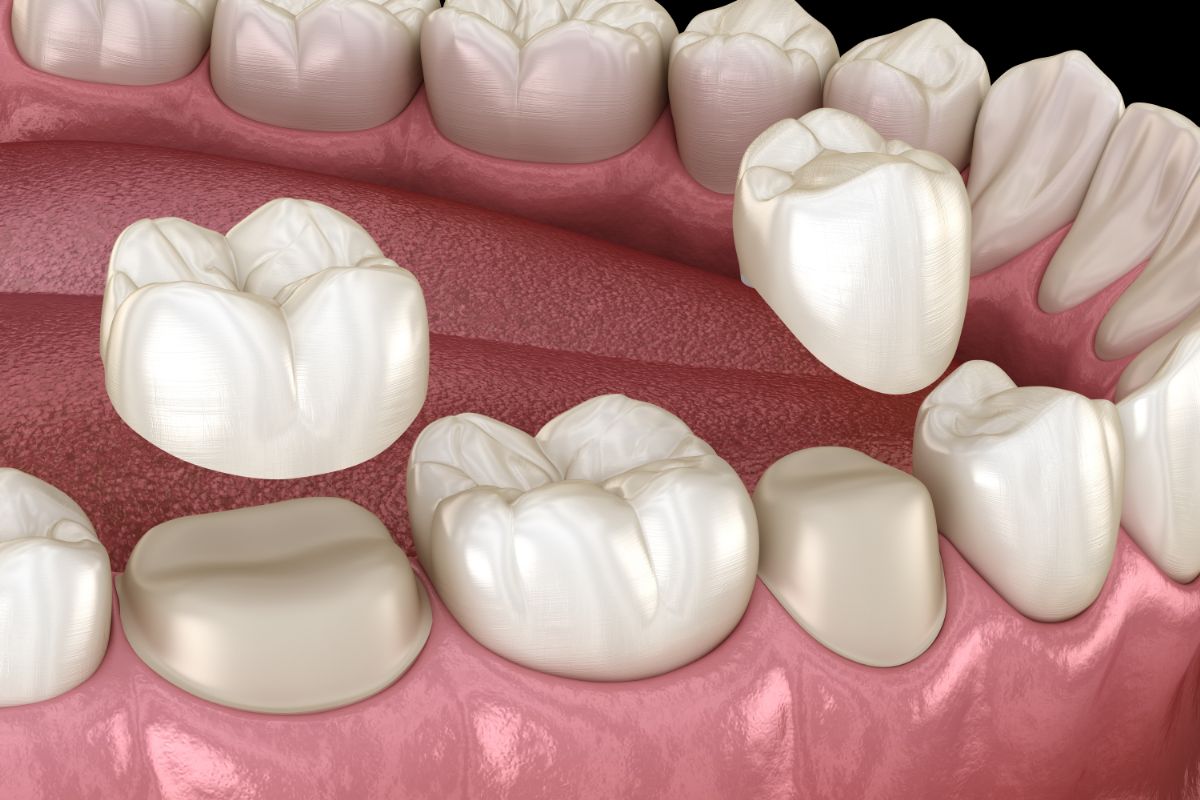

セラミック・

ジルコニア治療の特徴

天然の歯に近く透明感を再現しやすい。

特徴

セラミックよりも硬く、割れにくいため奥歯の治療の選択肢にもなる。

共通するメリットとして、金属を使っていないため、金属アレルギーの方でも選択できる素材であること、密着性が高く、二次むし歯を防ぎやすいことなどが挙げられます。

当院では、ご希望に応じてセラミック、またはジルコニアの詰め物や被せ物をご提案しています。

- 型取りと製作

- 装着と調整